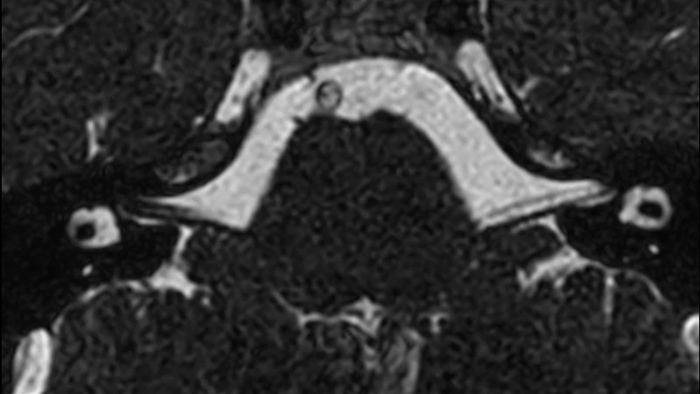

bFFE XD

Clinical application

Co-Creation Facility

Les Hôpitaux Universitaires de Strasbourg, France